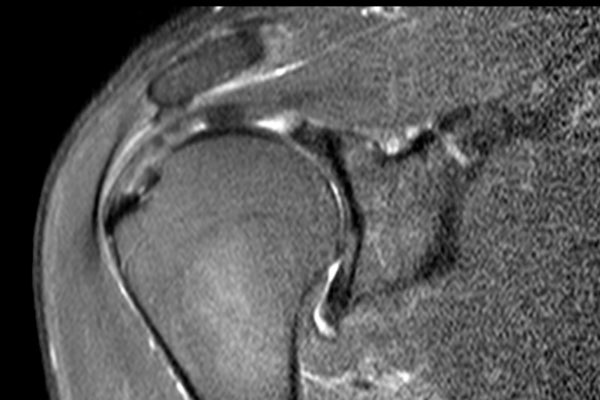

Nhấp vào hình ảnh để phóng to, sau đó cuộn qua các lát cắt.

Có hình ảnh rách toàn bộ chiều dày gân cơ trên gai kèm co rút và teo cơ.

Lưu ý các dải mỡ trong cơ tròn bé, cơ trên gai và cơ dưới gai.